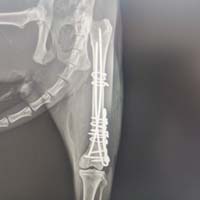

Yalıkavak veteriner kliniğimizde gerçekleştirdiğimiz ortopedik cerrahi uygulamalar:

Ortopedik cerrahi oldukça titizlik ve özen gerektiren cerrahi uygulamalardır. Diğer cerrahi disiplinlere nazaran asepsi ve antisepsi (sterilizasyon) konusunda ASLA hata kabul etmez. Eğer bu aşamada özensiz davranılırsa, postoperatif süreçte kemik dokunun iltihaplanmasına neden olup, kemiklerin kaynaması gecikmiş olur.